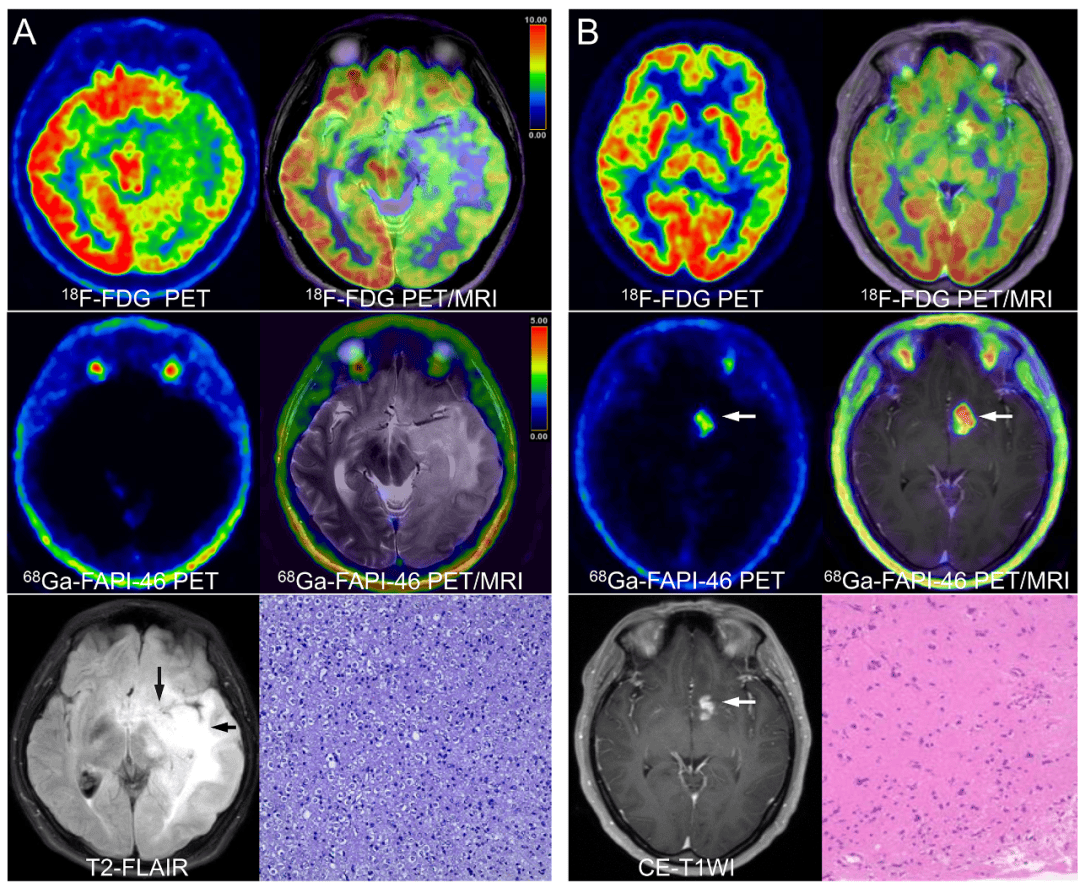

新华社伦敦5月22日电(记者郭爽)英国研究人员在新一期美国《神经肿瘤学杂志》上发表论文介绍,他们新开发出一种超快速脑肿瘤基因诊断方法,可以将脑肿瘤的诊断时间从此前的6至8周缩短至2小时。

这种脑肿瘤基因诊断方法由英国诺丁汉大学等机构的研究人员和临床医生共同开发。该方法基于牛津纳米孔技术公司的便携式测序设备,可更快检测人类基因相关区域,并可同时测序多个DNA区域,从而加快整个检测流程。

研究人员在50例脑肿瘤手术中使用了这一新方法,取得了100%的成功率,可在手术后两小时内提供诊断结果,并在基因测序几分钟内提供详细的肿瘤分类。